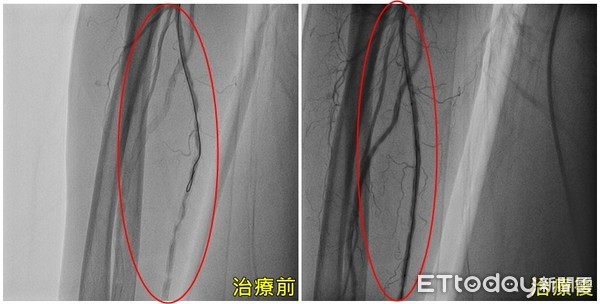

▲手術打通血管後,才讓手指恢復血色。(圖/亞大醫院提供)

亞洲大學附屬醫院心臟檢查室主任張育晟指出,患者罹患糖尿病及末期腎病,因長期洗腎,導致血液循環差,造成血液供應遠端組織的養分和氧氣不足,手指才會出現發黑疼痛的症狀。伍女雙手也因尺動脈及橈動脈血管多處狹窄和阻塞合併嚴重鈣化,需透過「導管周邊血管成形術」打通血管,才逐漸找回手指觸感與溫度,「若再晚一點就診,恐面臨截肢的命運」。

張育晟進一步解釋,周邊動脈阻塞性為動脈粥狀硬化所致,好發於中老年人,患有三高、抽菸、慢性腎病變、肥胖、家族史的民眾亦是高危險群,經評估患者的情況適合「導管周邊血管成形術」,利用動脈打針的微創方式,不需要開刀,打通狹窄和阻塞的血管,並使用氣球擴張或置放支架,術後大幅改善疼痛感,也能減少對止痛藥的依賴,使慢性傷口能夠加快癒合。